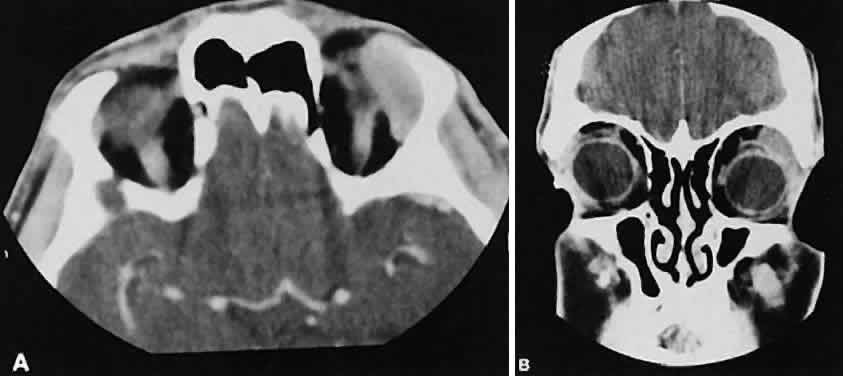

Fig. 6. Nonspecific inflammatory dacryoadenitis. An isodense enlargement of the lacrimal gland is noted on axial (A) and coronal (B) views. Note the similarity to Figure 18.

Fig. 18. Axial (A) and coronal (B) views of lacrimal gland lymphoma. There is homogenous enhancement of the enlarged lacrimal gland. Compared with Fig. 6, there is no difference.